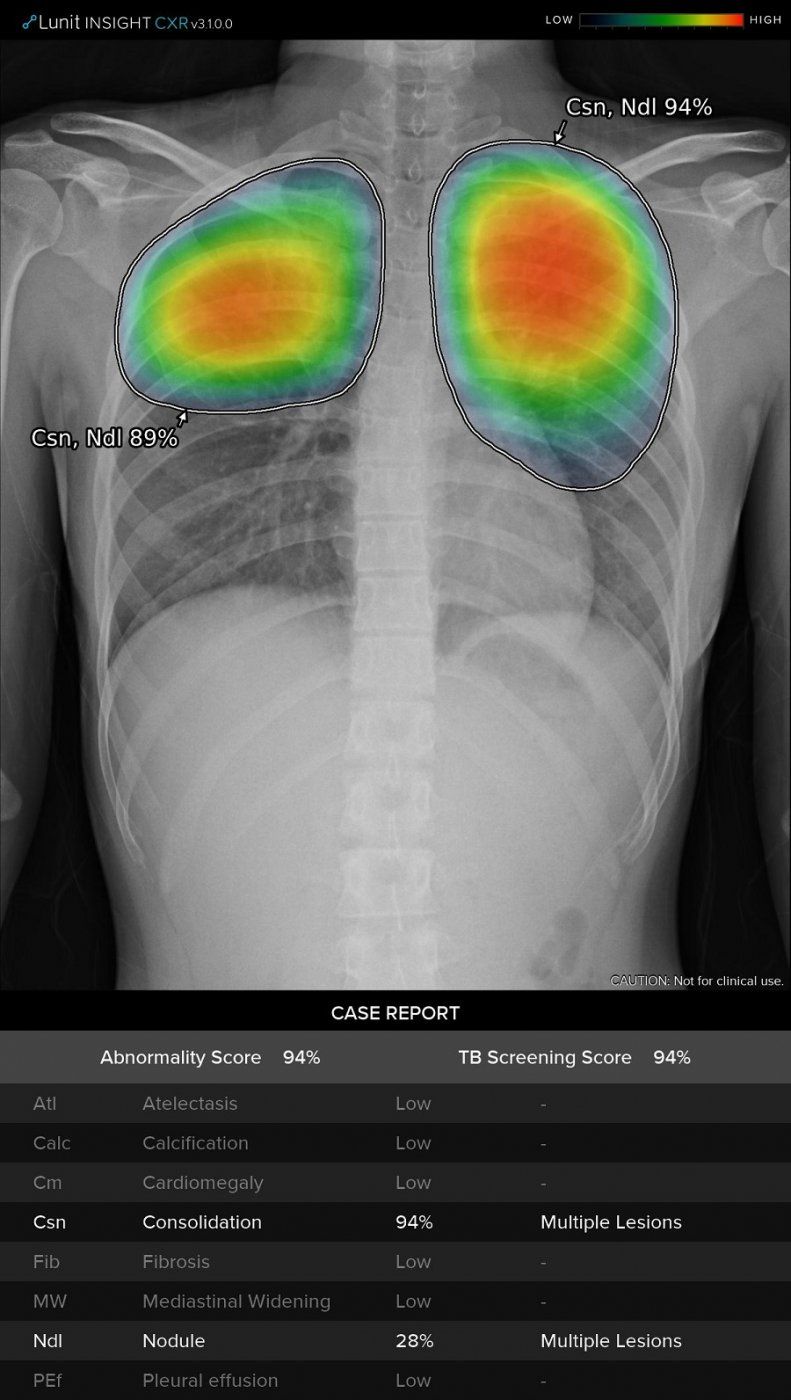

El Sistema Thoracic Care proporciona el apoyo tan necesario para ayudar a identificar rápidamente los casos de alto riesgo, así como para controlar la progresión o regresión de los síntomas respiratorios leves de los pacientes. Con una tasa de precisión del 97-99% (Área bajo la curva - AUC), los potentes algoritmos que hay detrás del sistema de IA han sido entrenados para detectar hallazgos radiológicos en segundos. En un estudio, los resultados mostraron una reducción del 34% en el tiempo de lectura por caso.